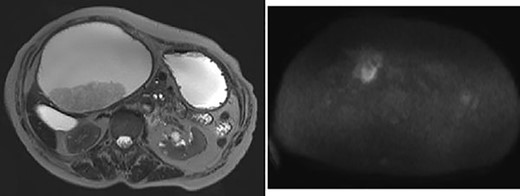

Upper gastrointestinal endoscopy showed severe duodenal stenosis due to compression from outside of the wall, which was the cause of gastric pain and anorexia (Fig. 3).

Upper gastrointestinal endoscopy showed severe stenosis of the duodenum.